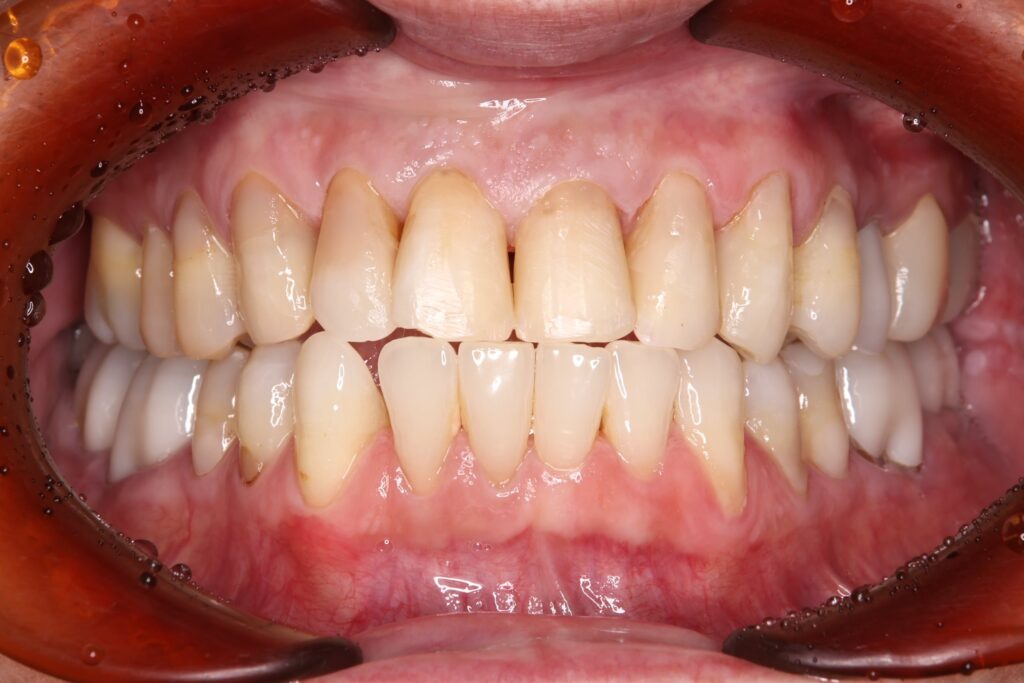

銀歯をすべてセラミックへ置き換え、あわせてホワイトニングを行ったことで、口腔内全体が明るく清潔感のあるお口元になりました。また審美的な向上が得られただけでなく、プラーク(細菌)が付着しにくい環境を整えることができた点も大きな成果です。

また、痛みや違和感の原因となっていた部位についても適切な処置を行ったことで、現在は違和感なく、安心して噛める状態が維持されています。

機能面と審美面の両面において、良好な治療結果が得られました。